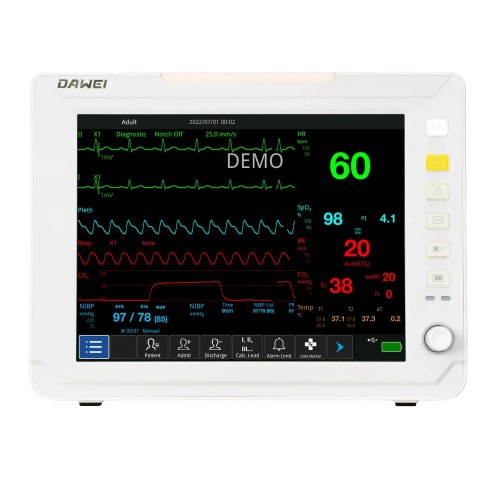

Patient Monitor - medexbio

Patient Monitor - medexbio

PATIENT MONITOR 5 PARMETERS

PATIENT MONITOR 5 PARMETERS

PATIENT MONITOR

PATIENT MONITOR

VITAL SIGN MONITOR

VITAL SIGN MONITOR

New E7 Portable Patient Monitor

New E7 Portable Patient Monitor

M10 vital signs monitor - Germany

M10 vital signs monitor - Germany

M20 vital signs monitor - GERMANY

M20 vital signs monitor - GERMANY

PROVIEW 10 PATENT MONITOR - GERMANY

PROVIEW 10 PATENT MONITOR - GERMANY

Patient Monitor for Adult Children Neonate

Patient Monitor for Adult Children Neonate

Dawei HM10 multi-parameter patient monitor

Dawei HM10 multi-parameter patient monitor

Superstarmed SP J12 multi-parameter patient monitor

Superstarmed SP J12 multi-parameter patient monitor